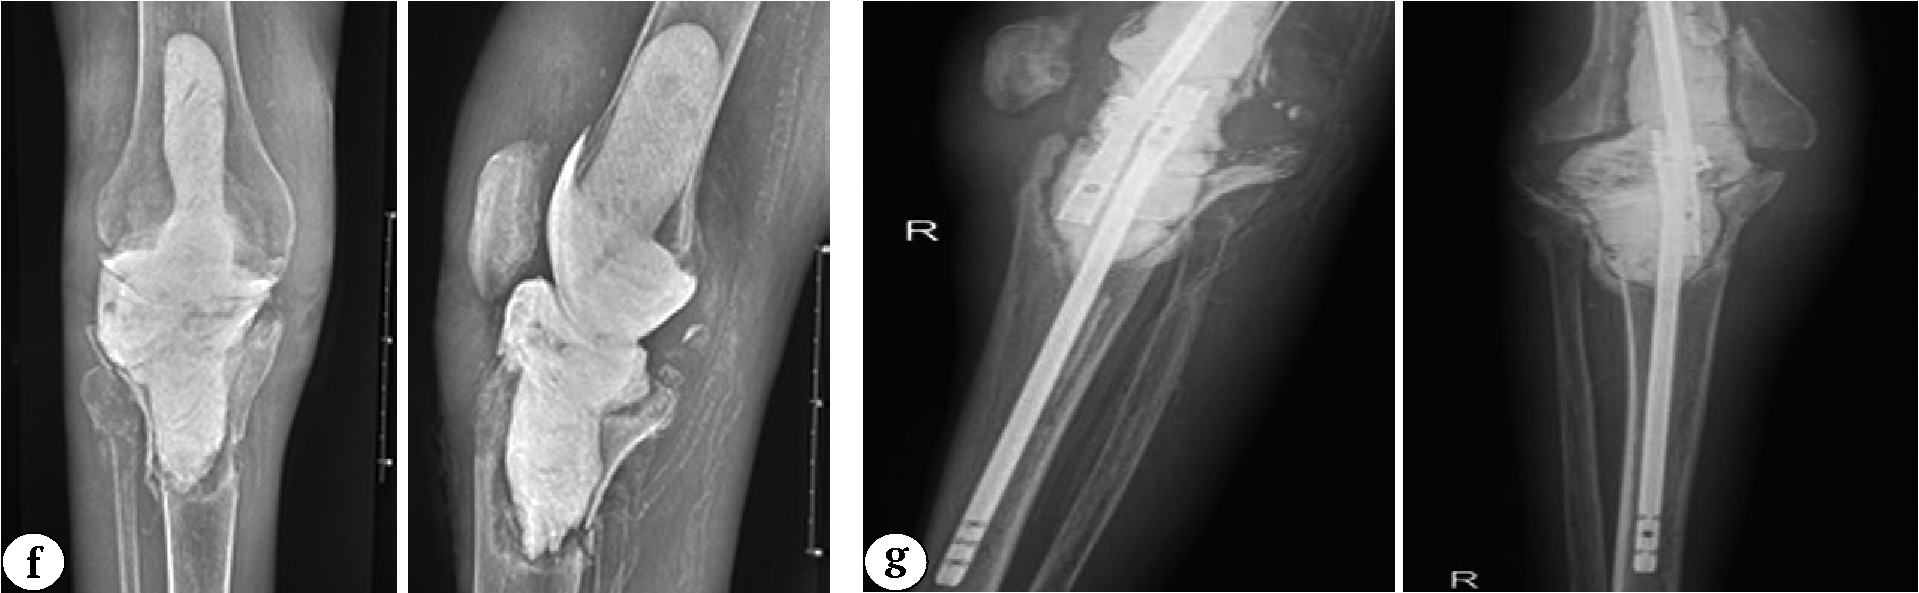

An example of a clinical case of aseptic loosening of the tibial component leading to infectious complications in a patient from Group 1 after primary knee arthroplasty is shown in Figure 3.

Fig. 3 (a, b, c, d, e). A 32-year-old man with secondary osteoarthritis of the right knee. Concomitant diseases: end-stage chronic kidney disease (5D stage), chronic hemodialysis for 7 years, type 1 diabetes: a — X-rays in two projections and CT scans before surgery: a bone defect is detected in the posterolateral part of the lateral femoral condyle b — knee after arthrotomy; c — X-rays after knee replacement (a revision femoral component and a standard 100 mm stem; the bone defect was replaced with two metal blocks of 5 mm and 10 mm, posterior-stabilized insert; standard tibial component); d — X-rays one year after knee replacement: no signs of osteolysis or component instability are observed; e — X-rays of the right knee three years after arthroplasty: radiolucent lines are noted in zones 3, 4, and 2 of the tibial component according to the KRESS (indicated by arrows)